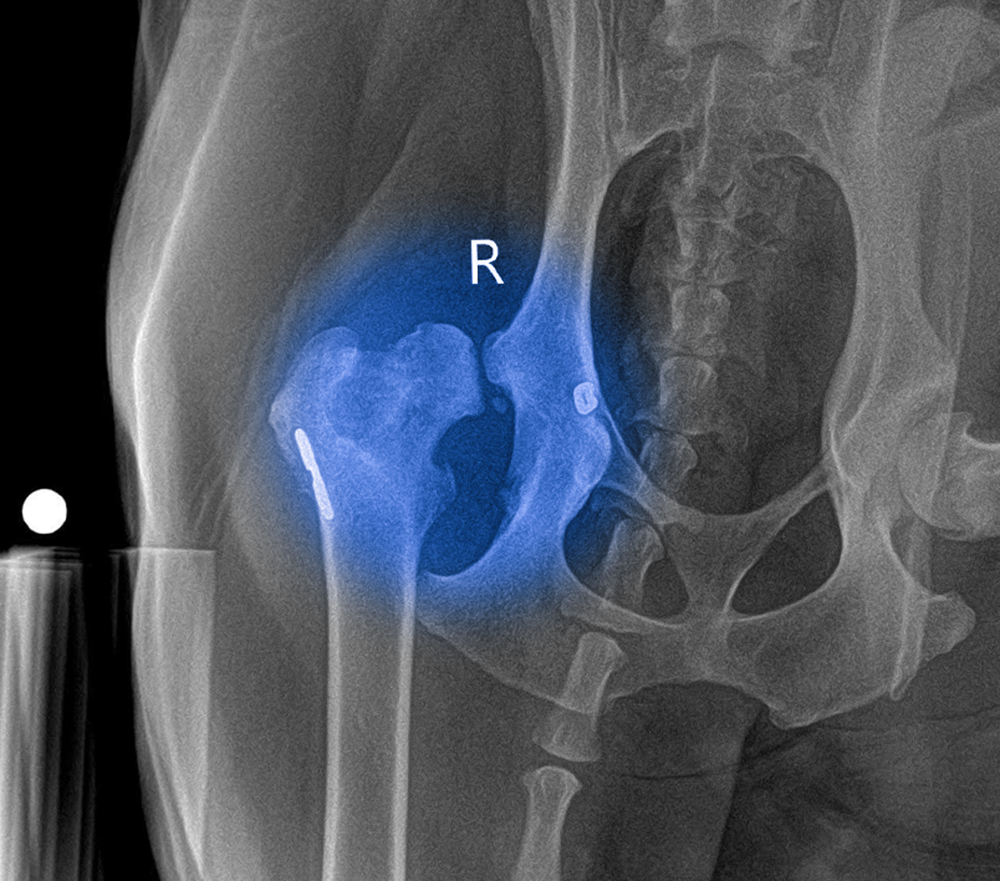

Qua thăm khám và hình ảnh X-quang, các bác sĩ phát hiện khớp háng của Sky đã bắt đầu tái tổn thương, dẫn đến thoái hóa ổ cối – vị trí tiếp giáp quan trọng giữa chỏm xương đùi và xương chậu.

Kết quả chiếu chụp cho thấy những hư hại nặng nề:

- Ổ cối đã bị xơ hóa nghiêm trọng.

- Cấu trúc khớp bị biến dạng.

- Mất kết nối hoàn toàn giữa chỏm xương đùi và xương chậu.

Chính điều này khiến khớp háng mất đi sự ổn định, gây đau đớn kéo dài và làm suy giảm nghiêm trọng khả năng vận động của Sky.

Quy trình thay khớp háng cho chó (THR) với công nghệ BlueSAO

Trước tình trạng tổn thương nặng và thoái hóa tiến triển, đội ngũ bác sĩ tại Bệnh viện Thú y Bằng Phạm đã quyết định chỉ định thực hiện phẫu thuật thay khớp háng toàn phần (Total Hip Replacement – THR)

Đây là kỹ thuật chỉnh hình tiên tiến giúp tái tạo hoàn toàn khớp háng, nhằm khôi phục vận động và loại bỏ triệt để cơn đau cho Sky.